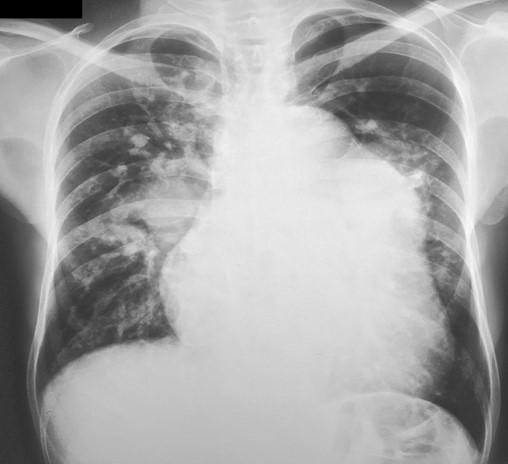

A Síndrome de Eisenmenger (SE) permanece uma entidade clínica complexa e desafiadora que cursa com hipoxemia crônica e envolvimento multissistêmico incluindo eritrocitose secundária geralmente associa…